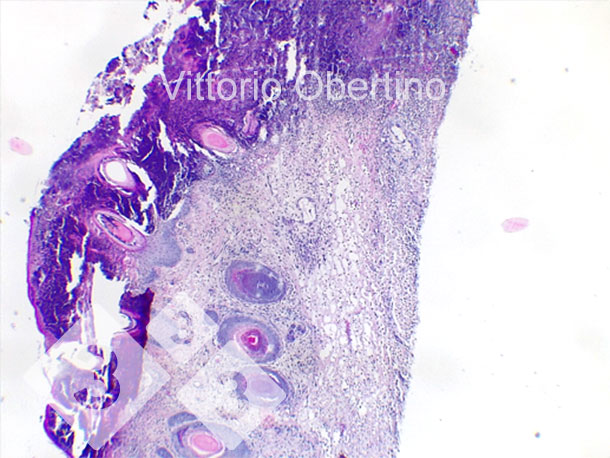

2- Des échantillons de tissus ont été envoyés à l'Université de Turin pour vérifier que les lésions étaient histologiquement compatibles avec les images décrites dans la littérature (Kuehling et al. 2020).

Figure 8. Nombril. Zone dermique localement étendue constituée de fibroplasie avec fibroblastes activés et de nombreux petits vaisseaux immatures (tissu de granulation nouvellement formé), infiltrat inflammatoire multifocal avec une prédominance de cellules lymphoplasmacellulaires ; dans certaines structures vasculaires, il existe un infiltrat inflammatoire granulocytaire qui entoure la paroi vasculaire et l'infiltre focalement (vascularite leucotarienne).